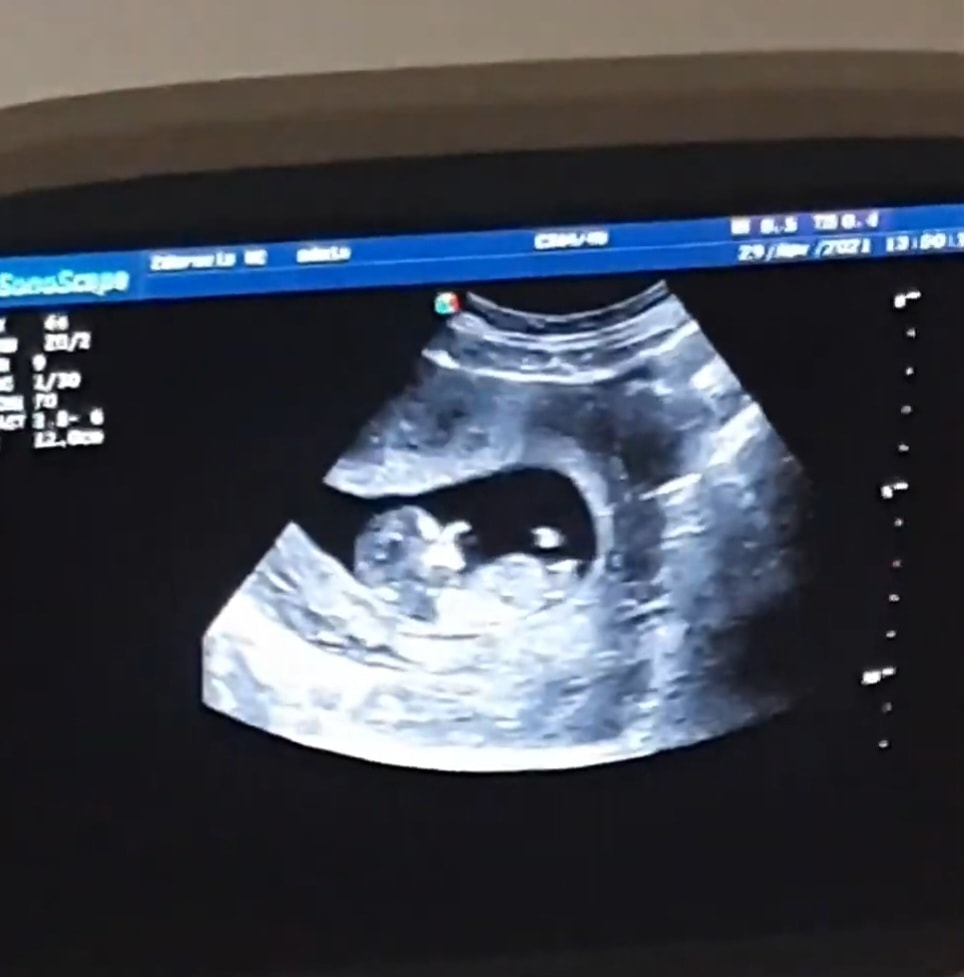

Половой бугорок в 10 недель 4 дня

Бугорок то есть в 10 недель, но предположить пол на этом сроке весьма сложно и сомнительно. Насчёт наклона - у младшего сына был вниз) И я потому думала, что может и девочка. Хотя врач предположил мальчика смотря снизу между ног. Оказалось, врач прав. Изображение

Пол Половой бугорок в 10-11 недель